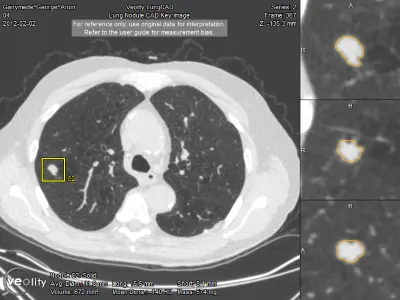

Veolity LungCAD bietet in der Lungenkrebsdiagnostik für Thorax CT-Aufnahmen eine vollständig integrierte KI-gestützte Detektion (CAD) solider Lungenrundherde.

Die Software ermöglicht eine zeiteffiziente und sichere radiologische Befundung von MSCT-Aufnahmen im klinischen Alltag. Veolity LungCAD verbessert die diagnostische Qualität in der Lungendiagnostik und macht komplexe Verlaufskontrollen einfach und effizient. Die besonders praktische automatische Segmentierung der Lungenrundherde mit Volumenmessung hilft Radiologen, reproduzierbare und vergleichbare Ergebnisse zu erzielen. Die Resultate werden einfach in die bestehende IT-Infrastruktur integriert. Radiologen profitieren von den automatischen CAD-Ergebnissen und behalten gleichzeitig die volle Kontrolle über ihren Diagnoseprozess.